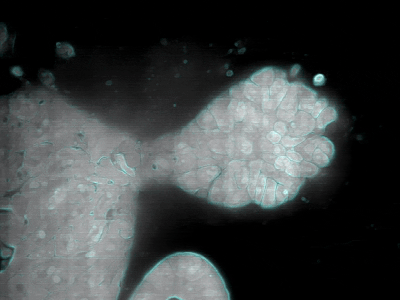

Project: Better tools to diagnose and understand Primary Ciliary Dyskinesia 13 February 202628 April 2026